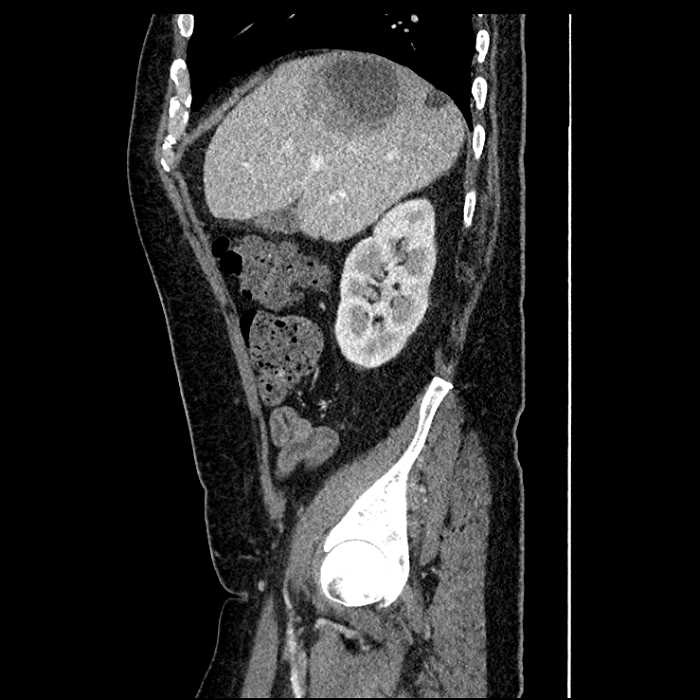

Age: 63

Sex: Male

Indication: Abdominal pain

• Large fluid density structure in hepatic segments 7 and 8 measuring 10 x 7 x 7 cm with internal septation and circumferential ill-defined low density compatible with edema

• Peripherally enhancing subcapsular collections along the anterior margin of the left hepatic lobe measuring 3 x 1 cm and 2 x 1 cm

• Clearly marginated fluid density structure in segment 7 and several other scattered tiny hypodensities, which likely represent cysts

Acute sigmoid diverticulitis complicated by a small contained perforation and a large abscess in the right hepatic lobe. Additional small subcapsular abscesses along the anterior margin of the left hepatic lobe.

• The classic CT imaging appearance is a double target sign with internal low density surrounded by an internal enhancing rim (capsule) and a low density external rim (edema)

Hepatic abscess showing the double target sign with low density internally surrounded by a thin inner enhancing rim (red arrow) and ill-defined outer low density rim (yellow arrow). Blue arrow indicates an internal septation. Red arrows: additional smaller subcapsular abscesses. Red arrow: focal contained perforation associated with diverticulitis.